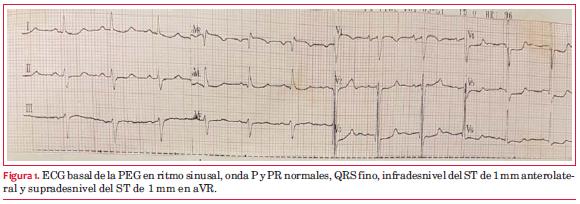

El ECG basal de la PEG presenta infradesnivel del ST de

Al máximo esfuerzo (